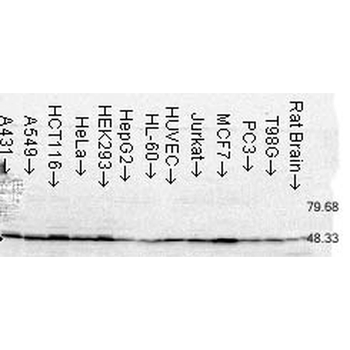

50 μl, 100 μl, 200 μlFKBP52 Antibody: APC [orb147210]

ICC, IF, IHC

Canine, Hamster, Human, Mouse, Rat

Mouse

Monoclonal

APC

100 μgFKBP52 Antibody: Biotin [orb147211]

ELISA, ICC, IF, IHC, WB

Canine, Hamster, Human, Mouse, Rat

Mouse

Monoclonal

Biotin

100 μg